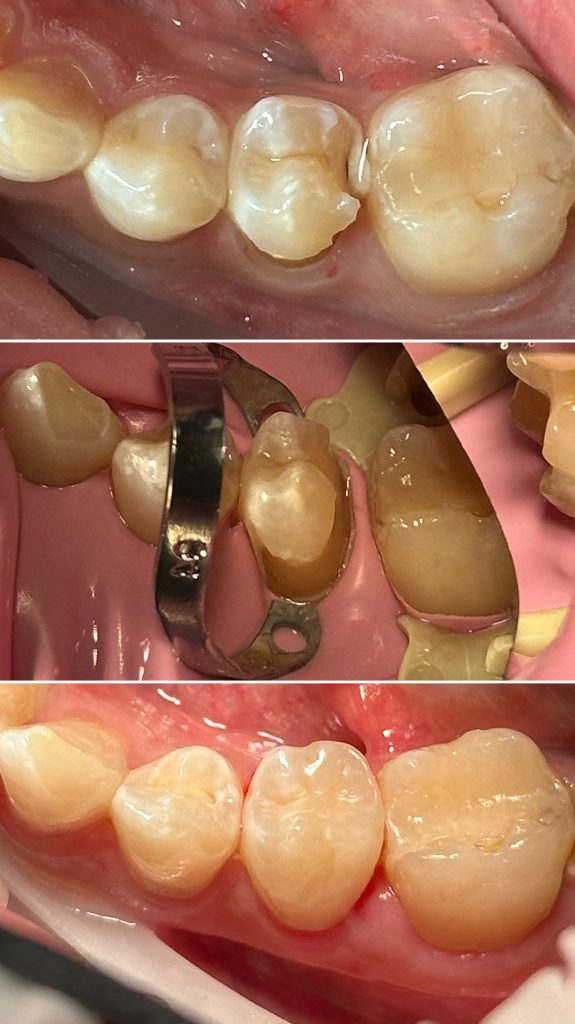

• Художественная реставрация фронтального и бокового участка зубов

2021 год – «Применение кофердама в стоматологической практике» учебный центр «Fenestra»

2022 год – «Прямая реставрация.Боковой сегмент.» Игорь Гудыма